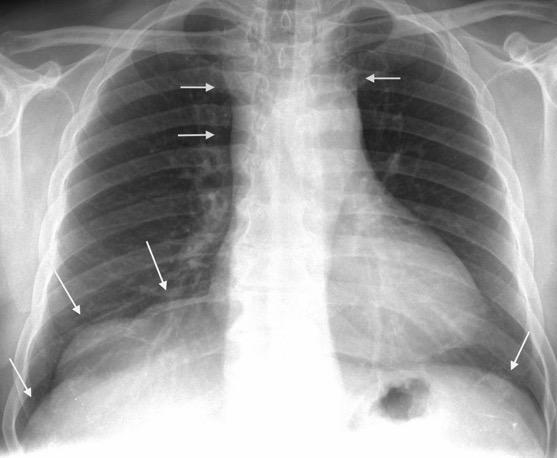

48. INVASIÓN DIRECTA DE CRURA DIAFRAGMÁTICA

51. METÁSTASIS DIAFRAGMÁTICAS